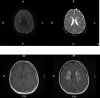

COVID-19-Associated Acute Multi-infarct Encephalopathy in an Asymptomatic CADASIL Patient